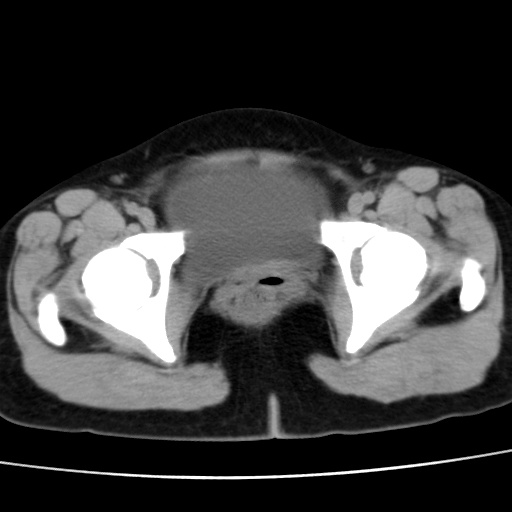

考虑多发子宫肌瘤,子宫直肠窝双囊性占位,另直肠周围脂肪密度增高,不知有何病史

子宫肌瘤,宫体部后方见液性密度影,是肠道还是子宫与直肠陷窝积液不好说,我觉得它的位置有点高

患者发热,而子宫直肠窝液性灶有明显边缘且局限且囊性,不除外为包裹性积液或脓肿

1)考虑子宫肌瘤可能性大。2)子宫后方囊性占位性病变,不排除卵巢囊肿可能。

考虑多发子宫肌瘤。子宫后方囊性占位性病变,不排除卵巢囊肿可能。